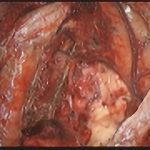

術中写真

摘出 前

摘出 中

摘出 後